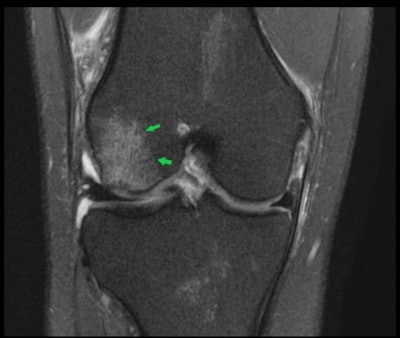

The figure below, for example, shows a T2-weighted image of the coronal view of the right knee. The female athlete has an acute pivot-shift injury with an acute lateral condylar bone contusion, which is highly indicative of an associated ACL tear.

Coronal fat-saturated proton density 3-tesla MRI of the right knee shows an acute pivot shift injury with an acute lateral condylar bone contusion. This is highly indicative of an associated anterior cruciate ligament (ACL) tear.The known predisposition in female footballers has no singular cause, but it is thought to be a mixture of anatomical differences, including the intercondylar notch, a groove at the bottom of the femur where it meets the knee, which is larger in men than in women; increased knee valgus, the Q angle formed between the quadricep muscles and the patella tendon; hip-width differences affecting knee alignment; gender biomechanics, such as joint flexibility, hormones, and menstrual cycles; plus potentially gender differences in early football training.